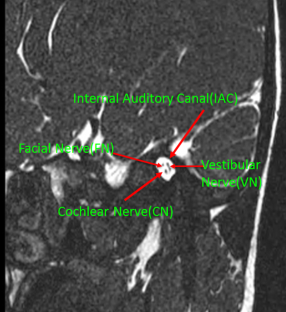

The main scope of this research is to present an automatic method to detect and segment the IAC and its nerves like the facial nerve, cochlear nerve, inferior vestibular nerve, and superior vestibular nerve. To address this issue, we propose a Mask R-CNN approach driven with U-net to detect and segment the IAC and its nerves. The Mask R-CNN with its backbone network of the RESNET50 model learns a background-based localization policy to produce an actual bounding box of the IAC. Furthermore, the U-net segments the structure related information of IAC and its nerves by learning its features.

Artificial intelligence (AI) in medical imaging is a burgeoning topic that involves the interpretation of complex image structures. The recent advancements in deep learning techniques increase the computational powers to extract vital features without human intervention. The automatic detection and segmentation of subtle tissue such as the internal auditory canal (IAC) and its nerves is a challenging task, and it can be improved using deep learning techniques.